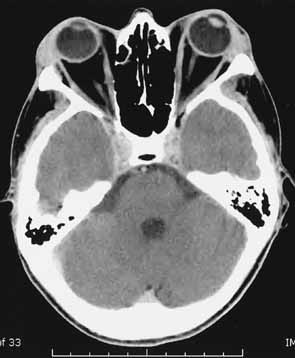

side in 50%.75 The most characteristic CT finding in thyroid orbitopathy is enlargement of the extraocular muscles, which is usually bilateral and symmetric and has a fusiform configuration, with sharply defined borders and sparing of the tendinous insertions. Atypical cases with tendon involvement and blurred muscle margins have been described.75 The pattern of muscle enlargement on CT parallels that seen clinically. The inferior rectus is the most commonly involved, followed by the medial rectus, superior rectus, and lateral rectus. Other findings include proptosis and anterior prolapse of the orbital septum due to excessive orbital fat and muscle swelling (see Fig. 4).76 Also, lacrimal gland enlargement and bone remodeling without erosion can occur.75 Patients at risk for developing optic neuropathy may also have severe apical crowding, a dilated superior ophthalmic vein, and anterior displacement of the lacrimal gland.68 Of these, apical crowding is the most sensitive indicator for the presence of optic neuropathy (Fig. 5A).56 Both axial and coronal CT cuts should be obtained; the coronal plane is needed to assess the enlargement of the extraocular muscles at the apex (see Fig. 5B). |